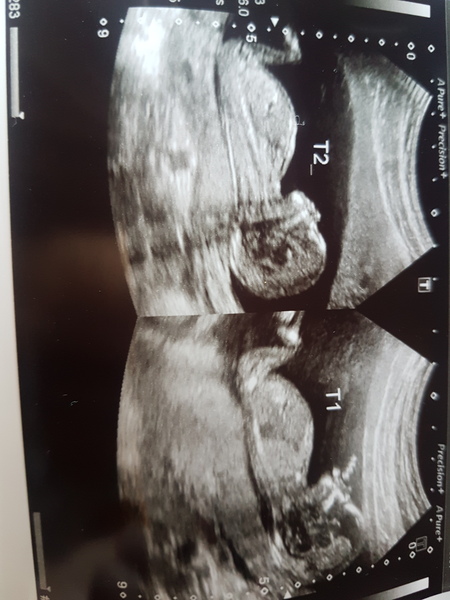

boodles101 · 10/03/2019 15:35

Had my nhs scan today put forward 6 days to 13+2 and had the massive shock that there's 2 babies in there!!